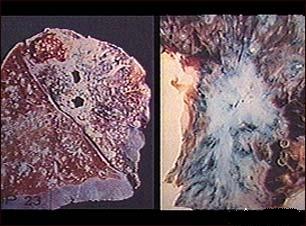

Tuberculoza (TBC) - generalitati